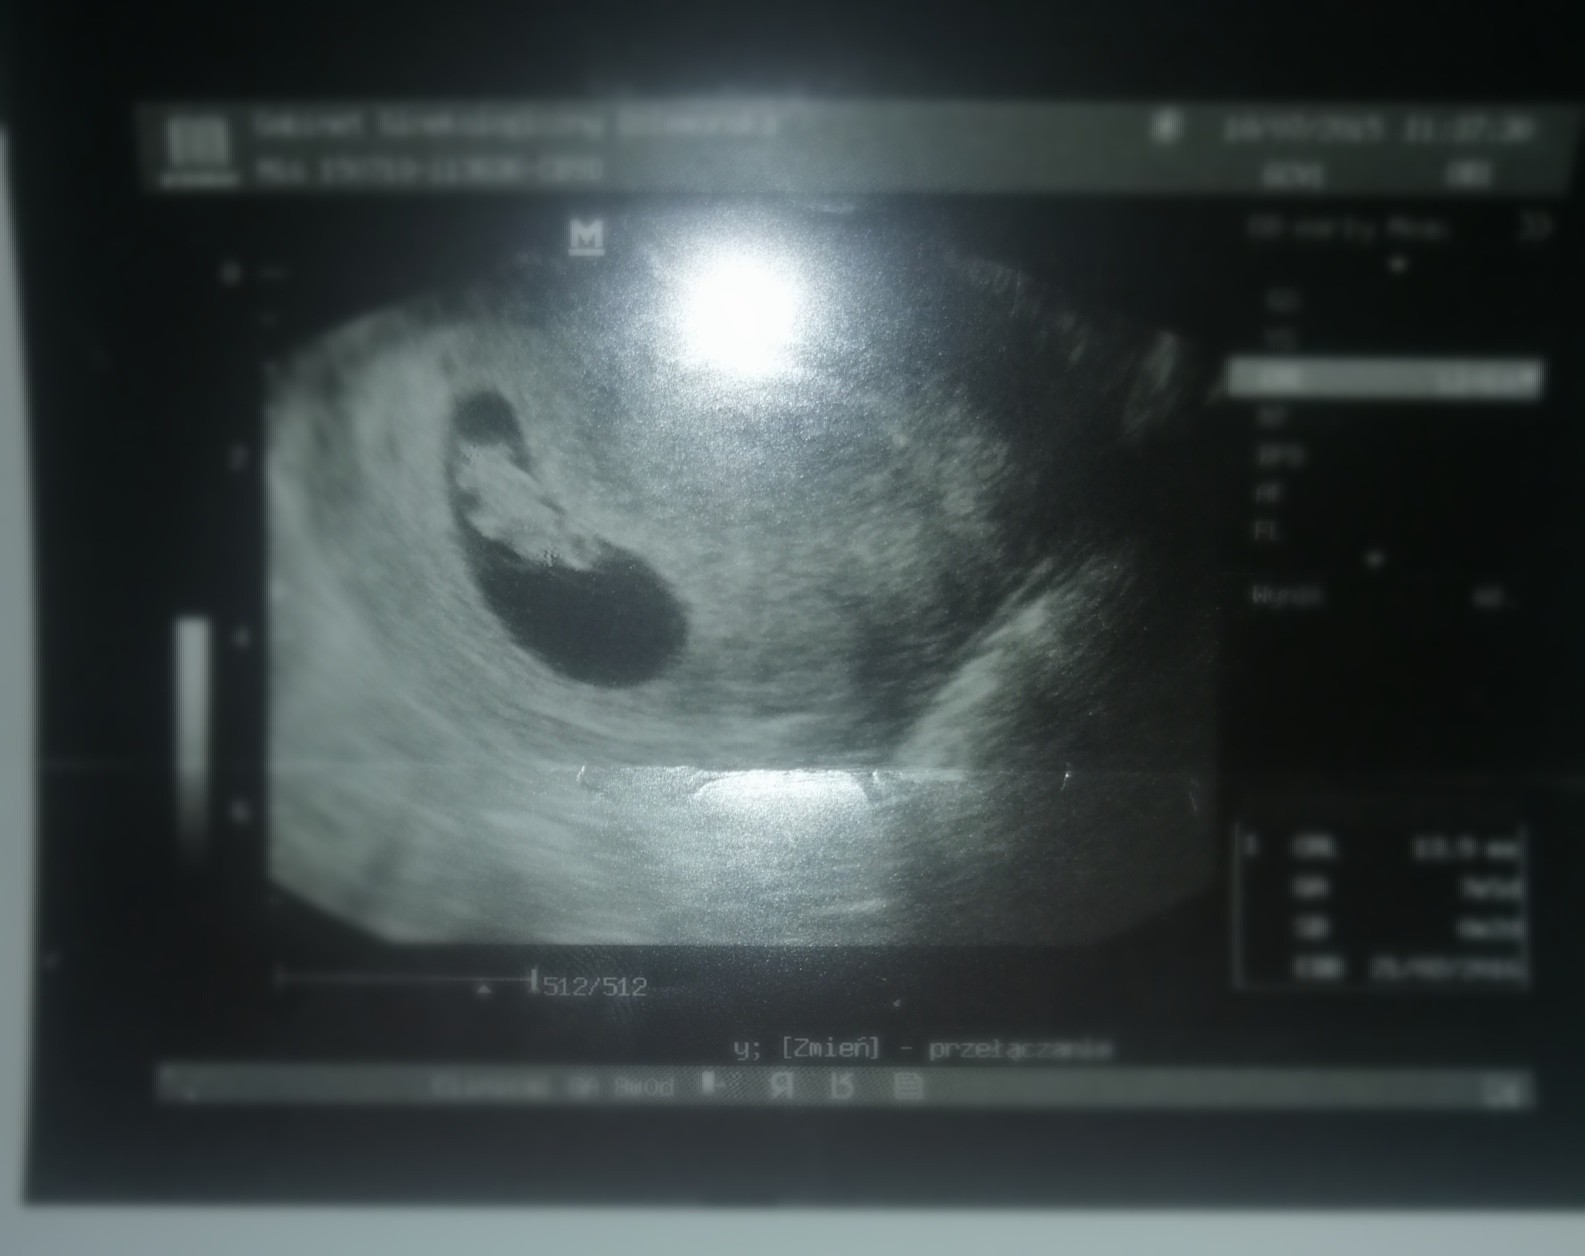

Zależy od organizmu. U mnie druga. Ale w pierwszej ciąży córka bardzo szy ko rosła. Już w 7 tyg miałam takie usgU mnie w zasadzie na razie nic nie widać, ale to moja pierwsza ciąża więc trudno mi nawet ocenić czy to normalne.